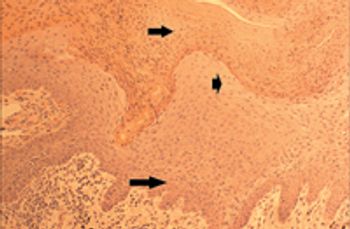

A systematic approach to a dermatologic diagnosis begins with a good history followed by a thorough physical examination.

Cutaneous cytology immediately and inexpensively reveals whether infectious, inflammatory, or neoplastic processes are affecting the skin, and it can help you determine which diagnostic path to continue on.